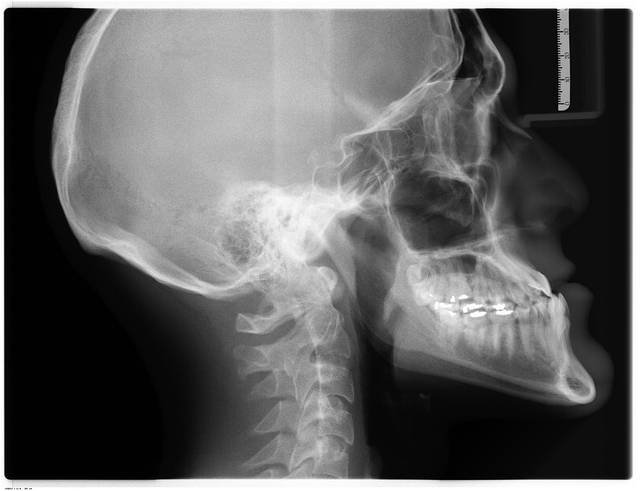

Ortodontia

Planejamento e acompanhamento durante todo o período de tratamento

Implante

Planejamento e estudo de caso para o melhor tratamento, incluindo reposição de massa óssea